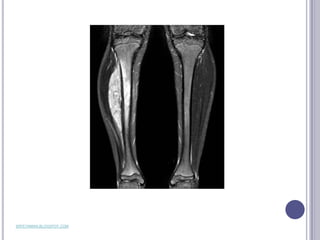

ÓSTEOSARCOMA

   Es el tumor óseo maligno más

frecuente   en     la   infancia   y

adolescencia, representando el

60%    de   los    tumores    óseos

malignos y un 5% del total de

tumores sólidos infantiles.

ÓSTEOSARCOMA  Es el tumor óseo maligno más frecuente en la infancia y adolescencia, representando el 60% de los tumores óseos malignos y un 5% del total de tumores sólidos infantiles. www.nlm.nih.gov